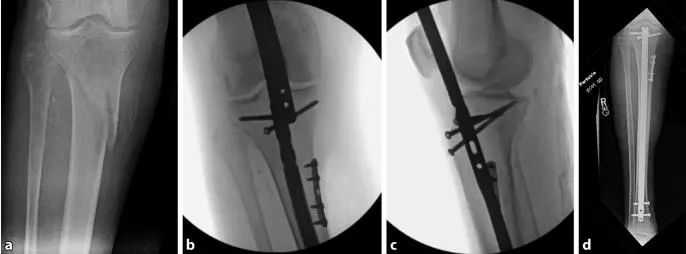

Основной причиной смещения при переломах проксимального отдела большеберцовой кости является деформация, вызванная растяжением сухожилия четырехглавой мышцы бедра во время сгибания колена и механическим конфликтом между кончиком ногтя и задней корой большеберцовой кости во время установки имплантата. Надколенник также препятствует осевому входу стержня в сагиттальной плоскости (рис. 1а, б). Поэтому другим распространенным методом введения в точку является медиальный парапателлярный разрез, в результате которого гвоздь вводится слегка медиально-латерально (рис. 1c и 2). Когда стержень входит в интрамедуллярный канал дистальнее перелома, проксимальная часть наклоняется в экзостоз (рис. 2). Наконец, напряжение покоя мышц передней камеры незначительно способствует эктропиону (рис. 3).

Рисунок 1 а, б. При использовании традиционного инфрапателлярного доступа надколенник предотвращает аксиальное вхождение стержня, что приводит к распространенной деформации переднего апикально-сагиттального выравнивания и эктропиона коронального выравнивания. c Интрамедуллярное выравнивание гвоздя выполнялось с использованием парапателлярного доступа.

Рисунок 2. Подход к точке входа через медиальный парапателлярный разрез приводит к введению гвоздя слегка медиально-латерально. Когда стержень входит в костномозговой канал дистальнее перелома (а), проксимальная часть изгибается в виде выпуклости (б)